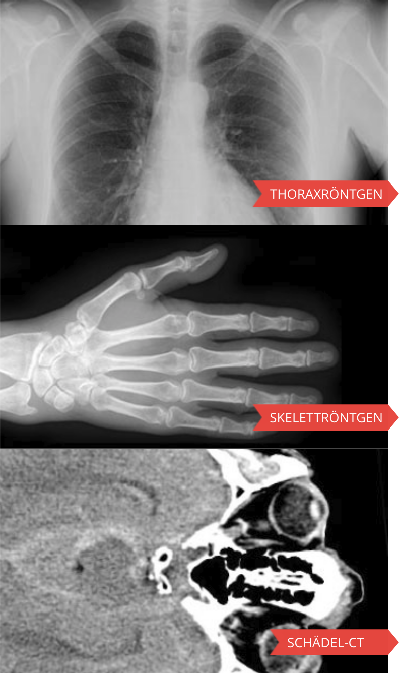

Berner E-Learning-Programme

Die wichtigsten Berner Lernprogramme können Sie direkt mit den links stehenden Verweisen aufrufen. Alle weiteren Lernprogramme finden Sie unter "zur Gesamtübersicht".